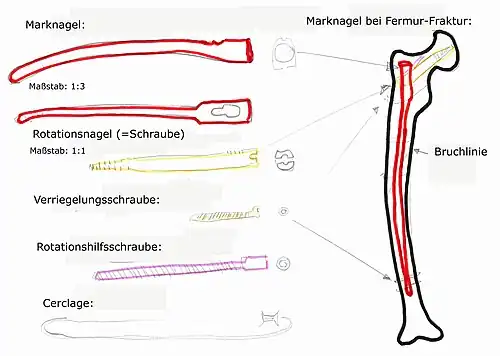

Schematische Darstellung eines Marknagels bei einer Oberschenkel-Fraktur

Der heutige Stand der Technik sind Marknägel aus weitgehend inertem Titan. Diese Implantate bieten die Möglichkeit einer statischen oder dynamischen Verriegelung sowie einer Kompression auf den Frakturspalt. Versorgt werden geschlossene und einfach offene Frakturen der großen Röhrenknochen (Oberschenkel (Femur), Schienbein (Tibia), Oberarmknochen (Humerus) ). Andere Versorgungen stellen Außenseiteranwendungen in Spezialfällen dar. Für gelenknahe Frakturen an oben genannten Knochen gibt es eine Reihe von Spezialimplantaten mit besonderen Eigenschaften wie z. B. den Gammanagel, proximalen Humerusnagel oder distalen Femurnagel. Die Implantate sind auf den Zielknochen anatomisch vorgeformt und in verschiedenen Dicken und Längen erhältlich.